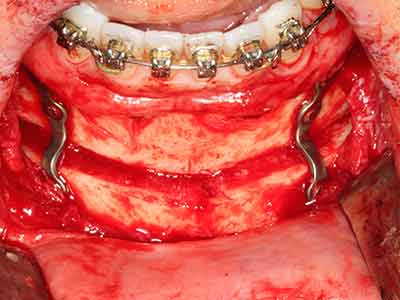

Piezosurgery has additional advantages when harvesting bone blocks. In addition to the high precision with osteotomy described above, the use of the thin saw tips specifically minimizes loss of material. Greater loss of material during harvesting can be expected with the thicker instrument tips, particularly when using Lindemann drills (Lakshmiganthan, Gokulanathan et al. 2012). The basal separation, which is necessary particularly for retromolar block transplants, is simplified by specially designed rectangular saws, with the result that piezosurgery is viewed as a precise, simple and safe procedure for harvesting retromolar bone blocks (Happe 2007) (Fig. 1-12).